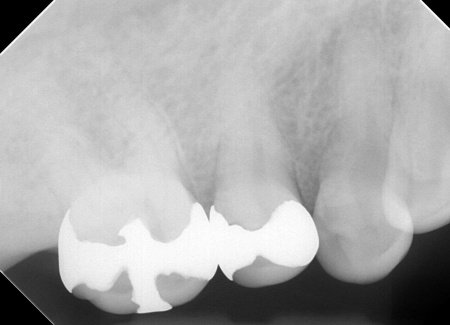

・左上奥歯

一番奥の歯は、詰め物が合っていませんでした。また、詰め物が外れたままの歯もあります。

・左上前歯2本

虫歯や、被せ物の不具合が見られました。

右上の歯には、見た目が自然で耐久性の高いセラミック素材「e-max」を用いて、アンレー(歯の一部を覆う詰め物)による治療を行います。

詰め物が合っていない左上奥歯2本は、強度に優れたセラミック素材「ジルコニア」を用いた修復を計画しました。